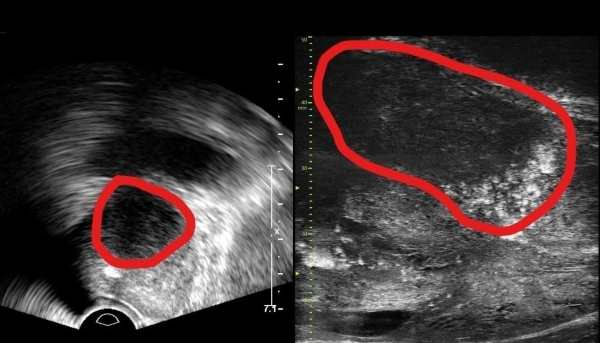

¡ã ±âÁ¸ Àü¸³¼± ÃÊÀ½ÆÄ »çÁø(ÁÂ)°ú ¸¶ÀÌÅ©·Î ÃÊÀ½ÆÄ »çÁø(¿ì)

±âÁ¸ ÃÊÀ½ÆÄ´Â Àü¸³¼± ºÎÀ§(µ¿±×¶ó¹Ì Ä£ ºÎºÐ)ÀÇ À½¿µ Â÷À̷θ¸ º´º¯À» È®ÀÎÇßÁö¸¸, ¸¶ÀÌÅ©·Î ÃÊÀ½ÆÄ´Â ³ôÀº ÇØ»óµµ¸¦ ÅëÇØ Á¾¾ç°ú ÁÖº¯ Á¶Á÷ÀÇ ¸ð¾ç±îÁö È®ÀÎÇÒ ¼ö ÀÖ´Ù.